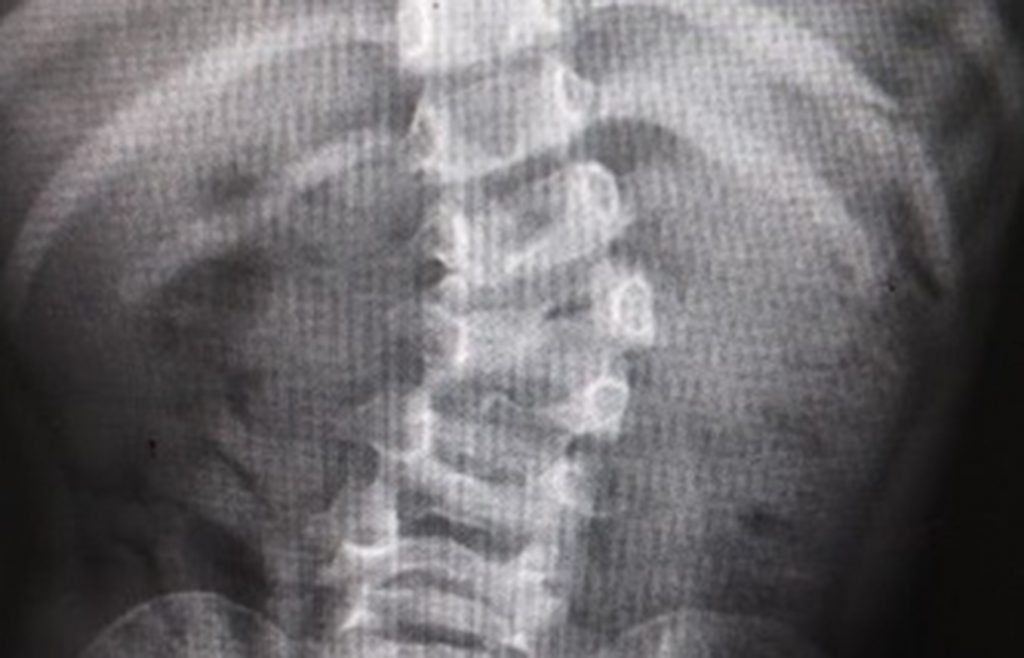

La paciente tenía su columna en forma de “S”, hombros y caderas desnivelados y la deformidad podía comprometer órganos vitales como pulmones o corazón

La pequeña Fátima tenía dificultades para desplazarse y mantener una buena postura, ya que su columna vertebral tenía forma de “S”, y sus hombros y caderas estaban desnivelados, pero al cabo de los meses y por la exitosa cirugía, a cargo del equipo multidisciplinario del IMSS, ahora es capaz de correr.

Dijo que el caso de Fátima fue peculiar, ya que a su corta edad ella presentó una escoliosis de tipo congénito, lo que quiere decir que una de sus vertebras no se desarrolló correctamente y esto ocasiona que un lado no crezca de manera equitativa.